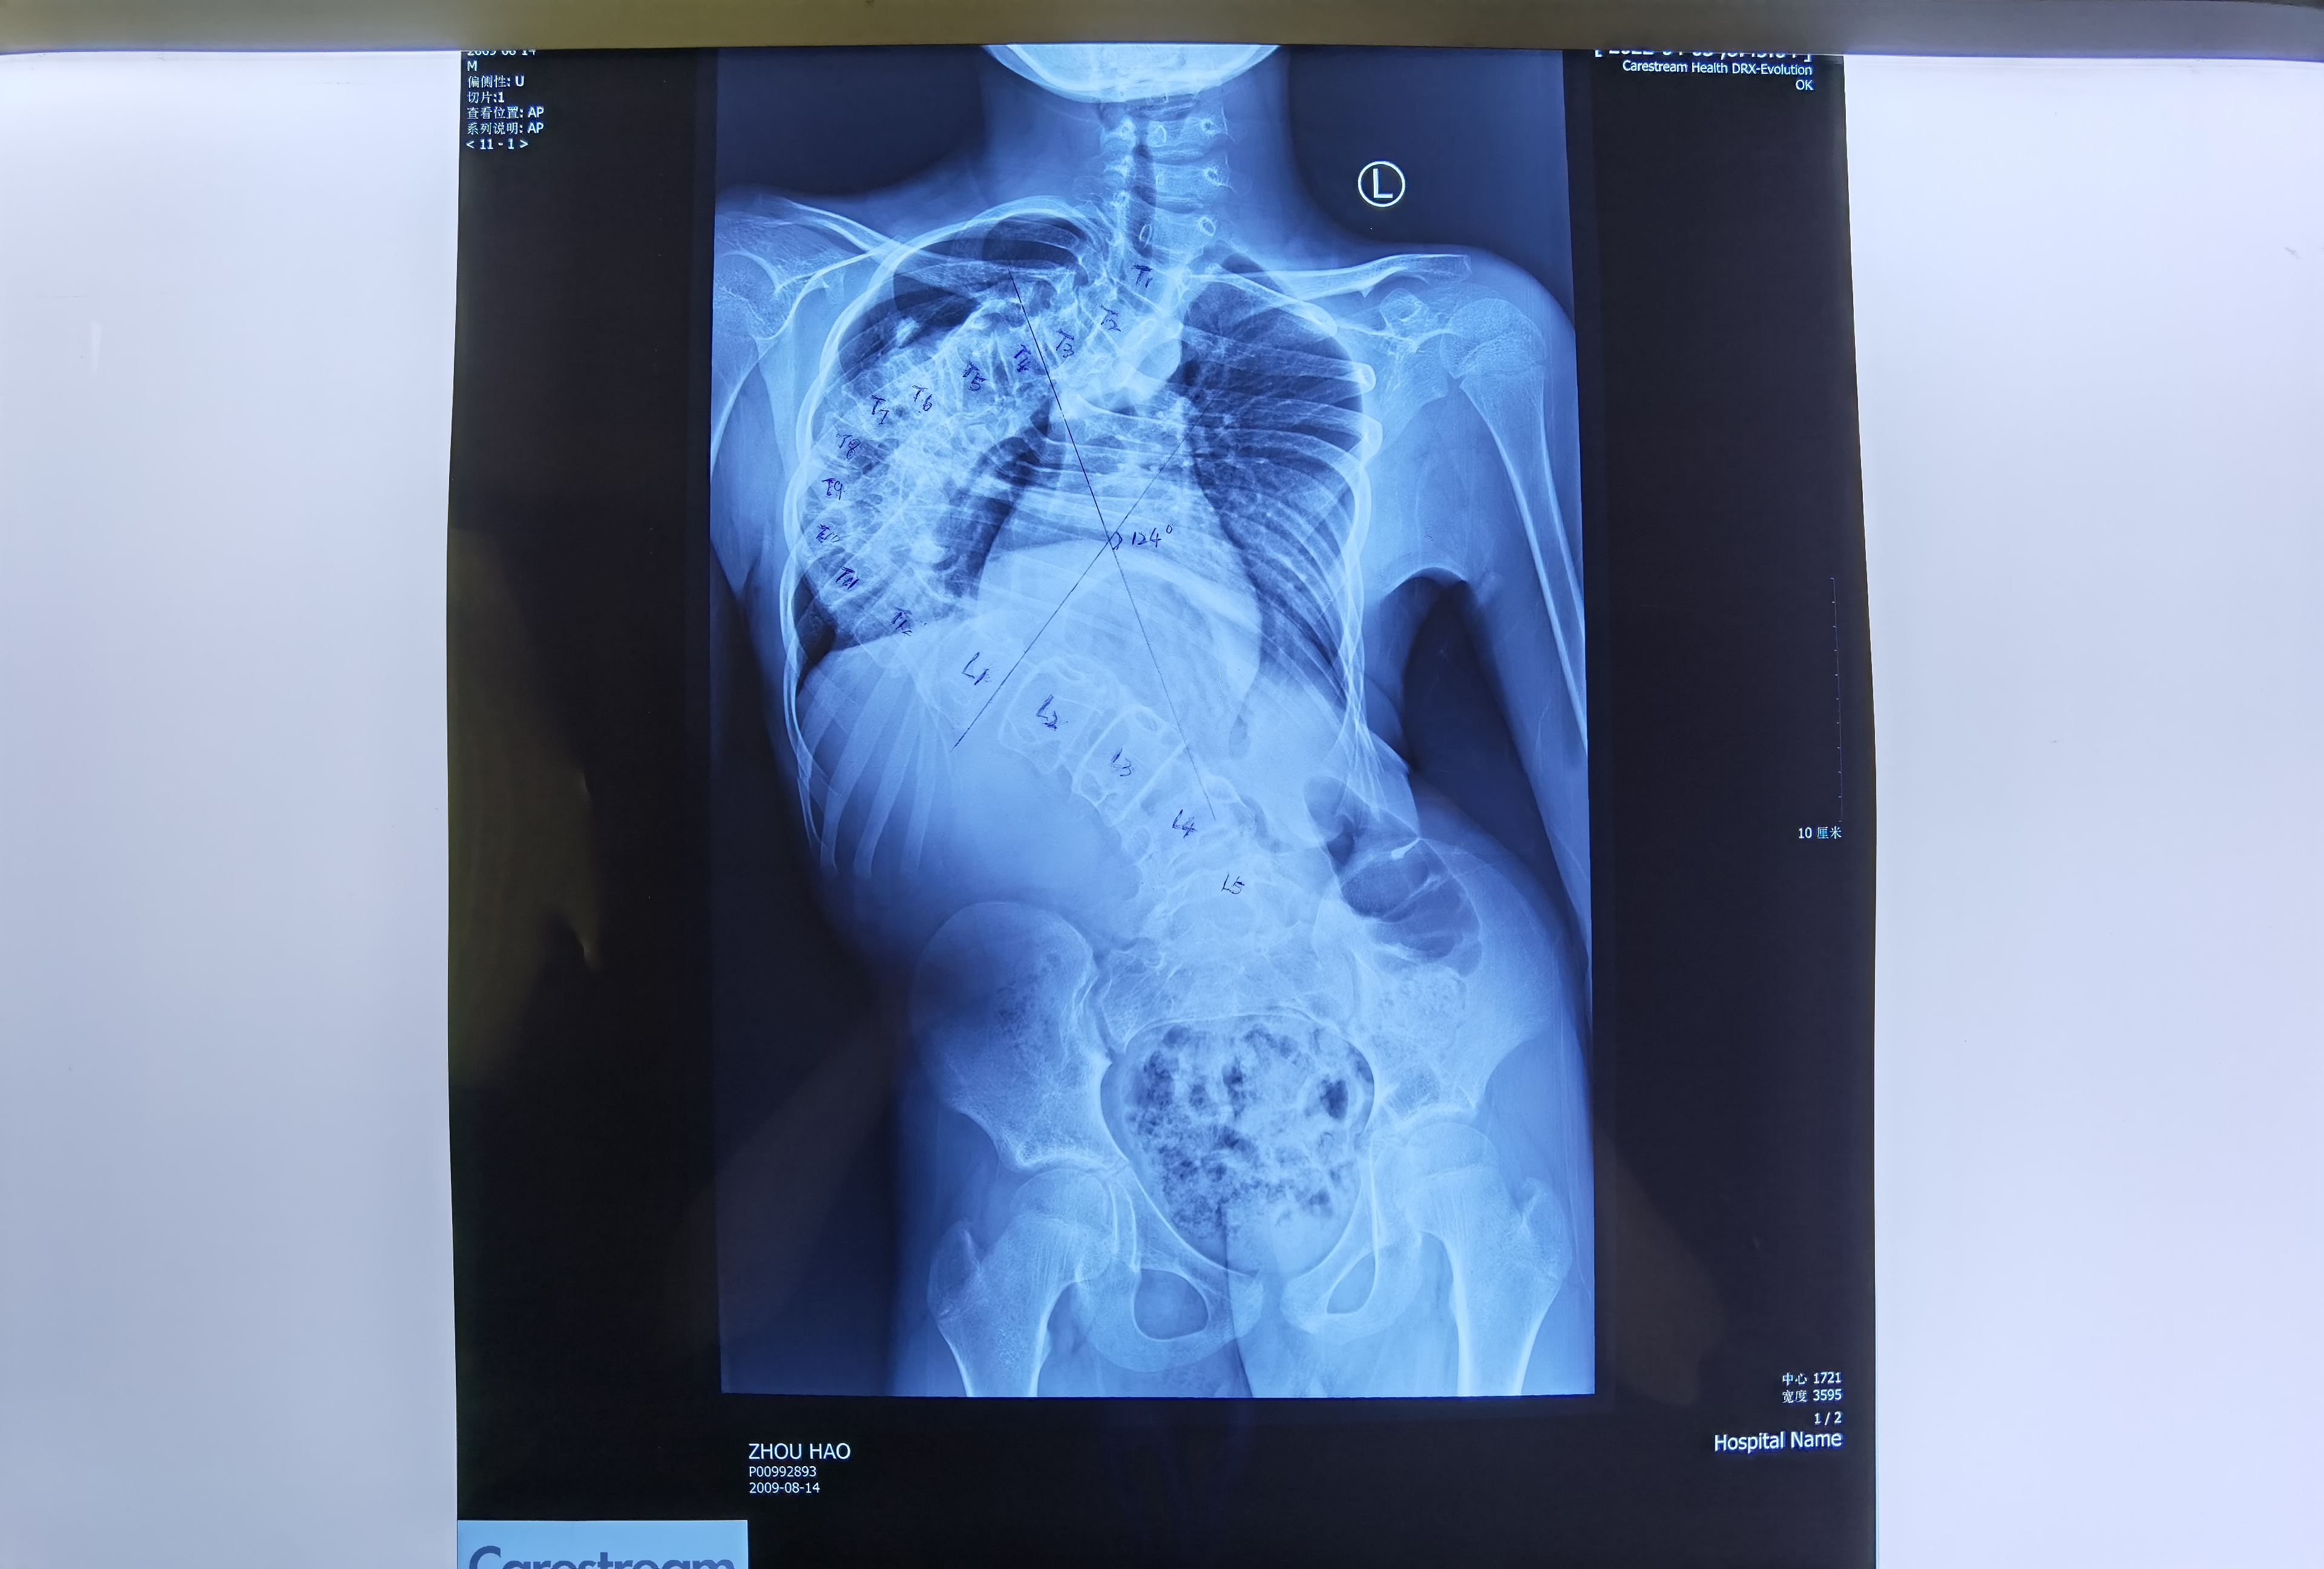

手术前

“通过术前术后的X光片对比可以看出,手术非常成功。”陈主任说。术前X光片显示脊柱以胸椎为中心向右侧呈明显侧弯畸形,侧弯角度COBB’S角为124度。右肩高,左肩低,骨盆倾斜,左侧骨盆高于右侧。术后X光片显示脊柱侧弯畸形得到明显的改善,脊柱侧弯角度COBB’S角为41度,较术前矫正了83 度,双肩部基本平齐,双侧骨盆基本平齐。